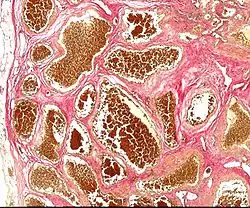

Histologisch bestehen Kavernome aus mittel- bis großlumigen pathologischen Blutgefäßen, deren dünne Wände häufig exzentrisch fibrosiert erscheinen. Im Gegensatz zu arteriovenösen Malformationen ist in Kavernomen weder eine arterielle noch eine venöse Differenzierung nachweisbar. In der Umgebung finden sich häufig Ablagerungen von Blutabbauprodukten (Hämosiderin) als Hinweis auf ältere Einblutungen. Trotz dieser Einschränkung ist ein Kavernom eine arteriovenöse Malformation und kein Hämangiom.[4]